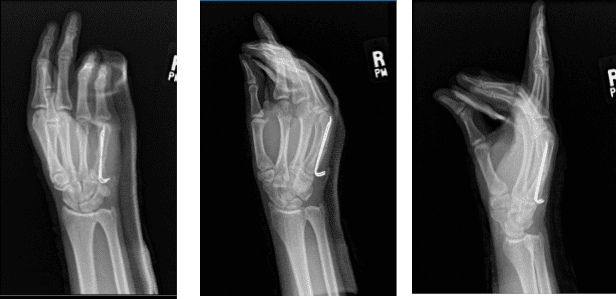

After two weeks post-operative, the patient came in with his Xray result. Two pins traverse a nondisplaced fracture middle one third right fourth metacarpal. Mild callus formation is noted. Fracture line is still appreciated.

An overlying cast is present. There are no subluxations nor dislocations. There are no radiopaque foreign bodies. Mild soft tissue swelling is noted. Healing fracture right fifth metacarpal, as above.

General Appearance: no swelling, tenderness, or warmth and wound clean and dry (small area of redness), appropriate range of motion, and neurovascular intact. Patients get well after surgery with consistent follow up checkups.